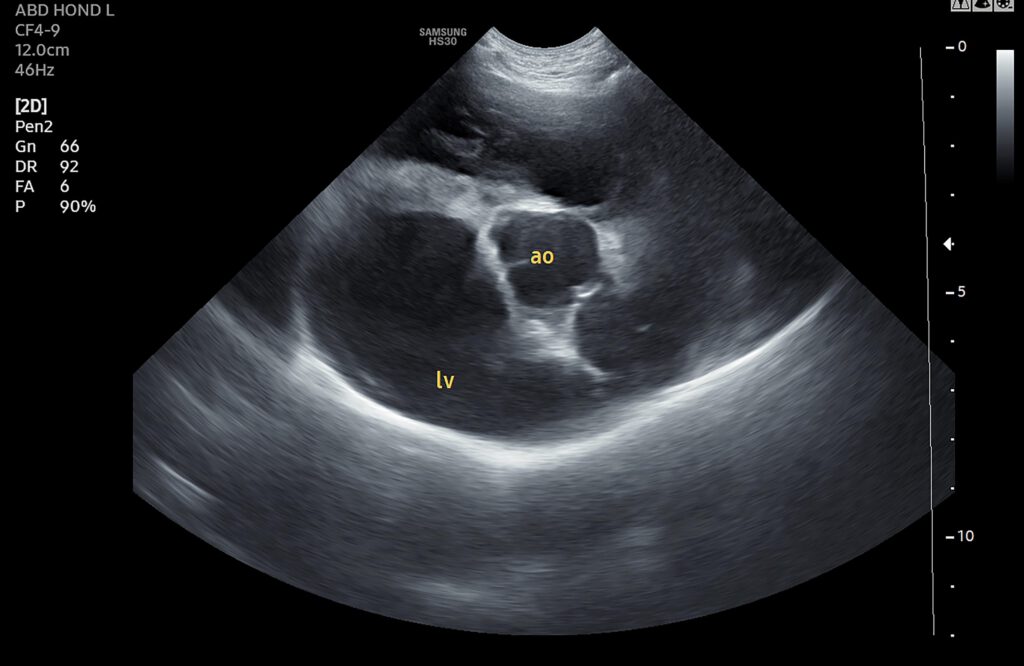

Met een hartecho kunnen we alle onderdelen van het hart goed zien, opmeten en de verhoudingen bepalen. Op deze manier kunnen we uitzoeken wat er precies mis is met het hart en hoe we het dier, waar mogelijk, kunnen helpen om het hart zo lang mogelijk zo goed mogelijk te laten werken. Dit is belangrijk, want net als bij mensen kan een hartprobleem bij dieren grote gevolgen hebben. Denk maar aan vocht achter de longen en vocht in de buik, maar er kan ook sprake zijn van problemen met de bloeddruk, de nieren of de schildklier.

De dieren liggen tijdens het onderzoek rustig op hun zij op een lekker dik kussen en laten het onderzoek vaak goed toe. Er wordt een klein stukje vacht geschoren ter hoogte van de rechter oksel zodat we het hart goed in beeld kunnen brengen.

We spreken samen met u een tijd af waarop u uw huisdier weer op kunt halen. Op dat moment staat de dierenarts u zelf te woord en bekijkt u samen de echobeelden. Op deze manier proberen we zo goed mogelijk weer te geven wat er aan de hand is met het hart en kunt u meteen samen met de dierenarts het behandelplan bespreken. Wat dit plan is, wisselt per patiënt en is dus niet van tevoren in te schatten. Wel willen we bij patiënten met een bewezen hartprobleem bij voorkeur, afhankelijk van het probleem, de echo (half)jaarlijks herhalen om veranderingen zo snel mogelijk te kunnen vinden.